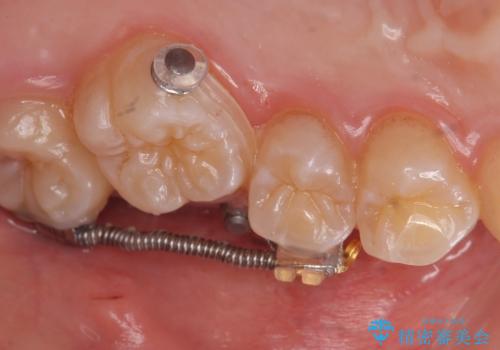

患者様が気づかない範囲で妥協して終わるということをせず、しっかり奥歯に部分矯正を用いて大きな問題を解決してからインビザライン治療に入りました。

奥歯のワイヤー部分矯正は位置的に人から気づかれることはないと思います。

奥歯までしっかり咬ませたい場合、矯正医を選ぶ場合は注意が必要です。

技術が不足しているドクターはマウスピース矯正のみで治療しようとするかもしれません。その方が術者は楽ですし、奥のかみ合わせは患者様も見えないためわかりずらいです。

妥協したゴールのみを目指すドクターではなく、時にはワイヤー部分矯正を使用してこだわりをもって治すドクターを選ぶとしっかり治るかもしれません。